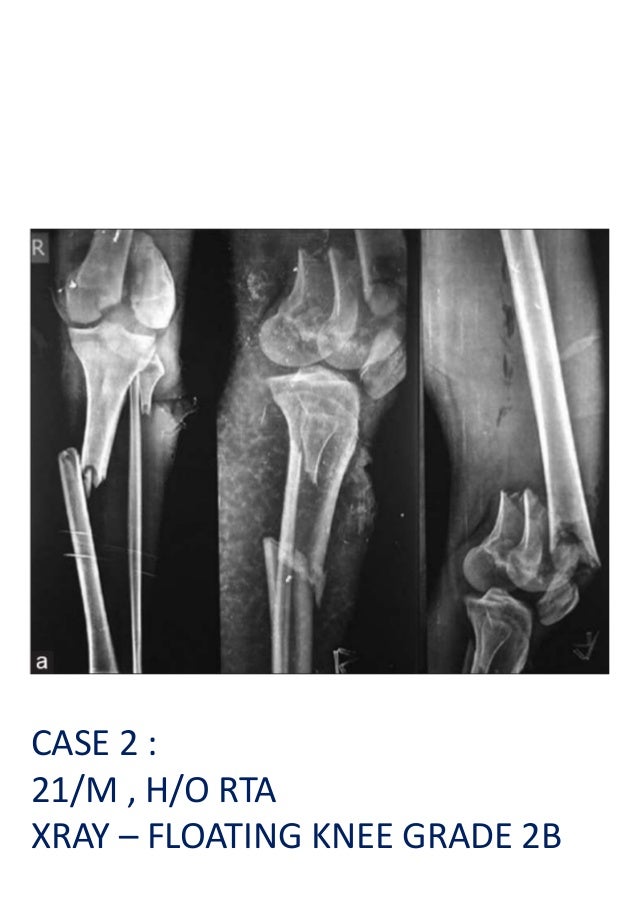

From www.slideshare.net

From www.slideserve.com